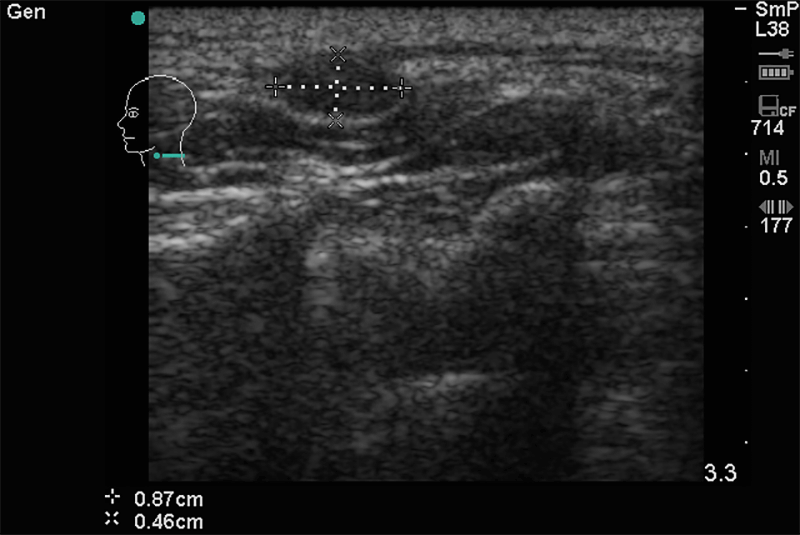

Alapvetően a pajzsmirigy, nyálmirigyek állapotának tisztázása mellett felvilágosítást ad a nyaki nagyerek állapotáról. Kimutathatóak a kóros nyirokcsomók, nyelvgyök körüli, szájfenék alatti, garatkörüli kóros elváltozások.

A nyaki régióban megjelenő kóros duzzanat, csomó fájdalommal vagy anélkül, szorító érzés a torok tájékán, rekedtség és esetleg nyelési zavar utalhat az itt található szervek kóros folyamataira.